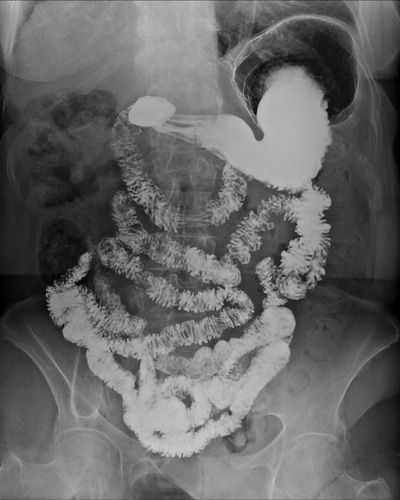

Lo studio radiologico dell’apparato digerente si basa sulla somministrazione orale di solfato di bario, un mezzo di contrasto che rende ben visibili le strutture interne agli esami con raggi X. Il paziente viene invitato a bere alcuni sorsi del preparato mentre il radiologo osserva il movimento del contrasto lungo il canale alimentare. Questa visione dinamica consente di analizzare il comportamento dell’esofago, la distensibilità dello stomaco e il passaggio verso il duodeno, offrendo un quadro completo della funzionalità del tratto superiore del sistema digestivo.

L’esame è indicato quando vi è la necessità di chiarire alterazioni strutturali o funzionali. Può essere utile per identificare ernie iatali, processi infiammatori, dislocazioni organiche, stenosi, disturbi motori o ulcerazioni. È inoltre impiegato per approfondire sintomi come dolore toracico o addominale, pirosi, difficoltà nella deglutizione, vomito ricorrente, senso di pesantezza dopo i pasti o calo dell’emoglobina dovuto a sanguinamenti non evidenti. In tutti questi casi, lo studio offre una rappresentazione chiara delle anomalie e facilita un inquadramento clinico accurato.

Prima dell’indagine il paziente viene invitato a indossare un camice monouso ed eliminare ogni oggetto metallico, che potrebbe alterare le immagini radiografiche. Una volta posizionato sull’apparecchio, gli viene somministrata una polvere effervescente che facilita la distensione delle cavità da osservare. Successivamente vengono assunti alcuni sorsi di mezzo di contrasto, mentre il radiologo guida il paziente in diverse posizioni per ottenere una completa verniciatura delle pareti degli organi. Durante le acquisizioni è fondamentale rimanere immobili e trattenere brevemente il respiro per garantire immagini nitide. L’esame dura mediamente dai dieci ai venti minuti, in base alla collaborazione del paziente e alla complessità del quadro clinico.